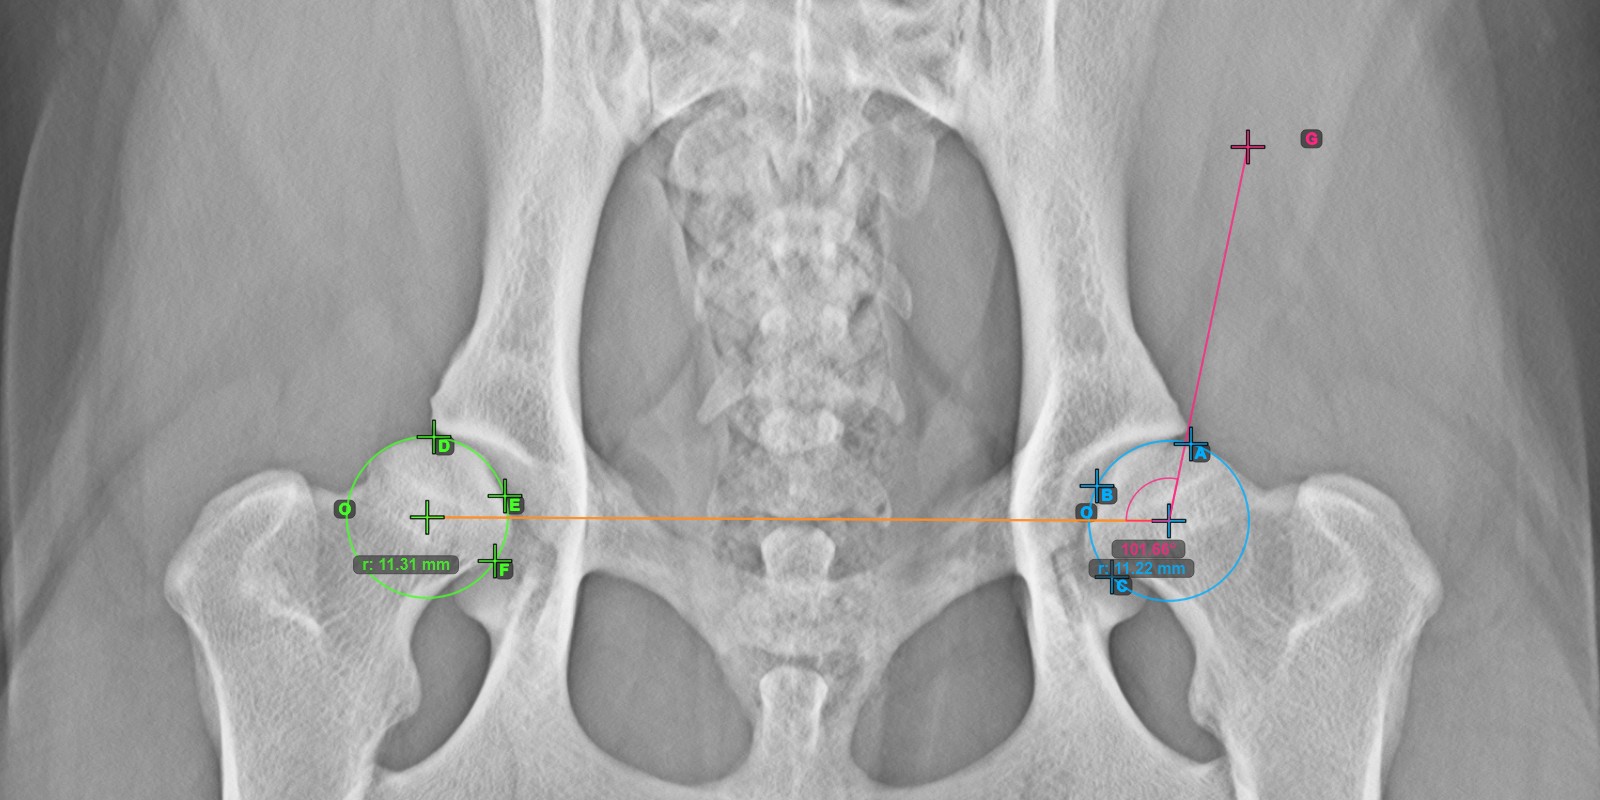

The Norberg Angle is usually used to assess hip joint laxity and detect hip dysplasia. This measurement requires a radiology image of the patient’s pelvis. Select the Norberg Angle measurement from the Advanced Measurement menu and assign the left mouse button to

Das untenstehende Bild zeigt die typische Platzierung der drei Punkte auf der Gelenkfläche des linken Caput Femoris.

../../_images/image266.jpg